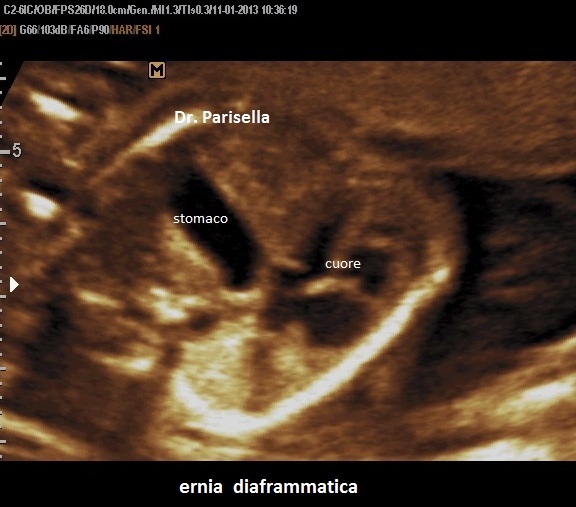

La Sindrome di Gershoni-Baruch รจ una rara malformazione congenita multipla caratterizzata da onfalocele, ernia diaframmatica, anomalie cardiovascolari e difetti radiali.